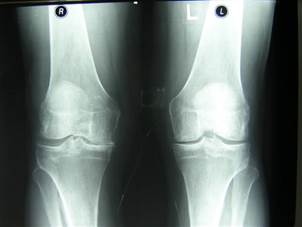

Науқас 45 жаста тізе буынындағы ауырсынуға шағымдануына байланысты рентгенография жасалынған. Диагноз:

+Е) Деформирлеуші остеоартроз